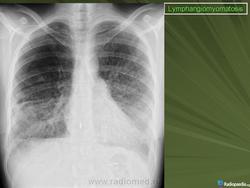

лимфангиолейомиоматоз

Типичный пример патологии при которой основным патерном являются кисты - :

Лимфангиомиоматоз.